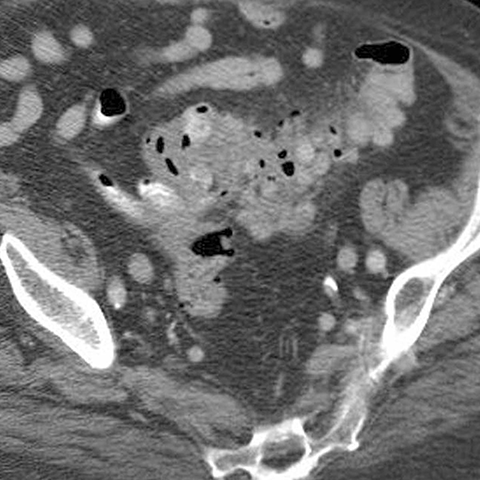

65 year-old male presents with fever and LLQ pain. [2 of 5]